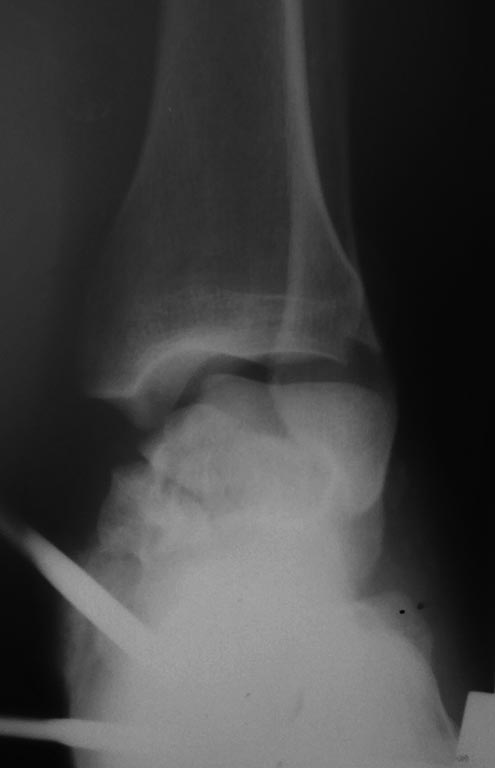

Перелом тела таранной кости.Первичнй артродез . |

Глубокоуважаемые коллеги! Просим поделиться опытом и по возможности отдаленными результатами лечения пациентов c подобными повреждениями. Пациент С. 28 лет строитель с вредными привычками,пострадал 1 05 17. Стабилизировали в АВФ,лечим мягкие ткани.По нашему мнению, положительные результаты (особенно отдаленные) реконструктивных операций при подобных повреждениях - сомнительны, склоняемся к первичному артродезированию ретроградным стержнем.Каковы Tips & Tricks,в данной ситуации, необходимо учесть? Какова вероятность лизиса девитализированных фрагментов, ипонадобится ли в последующем костная пластика? Благодарю за участие! С Ув.Илья

Дублирую Ро и СКТ

СКТ